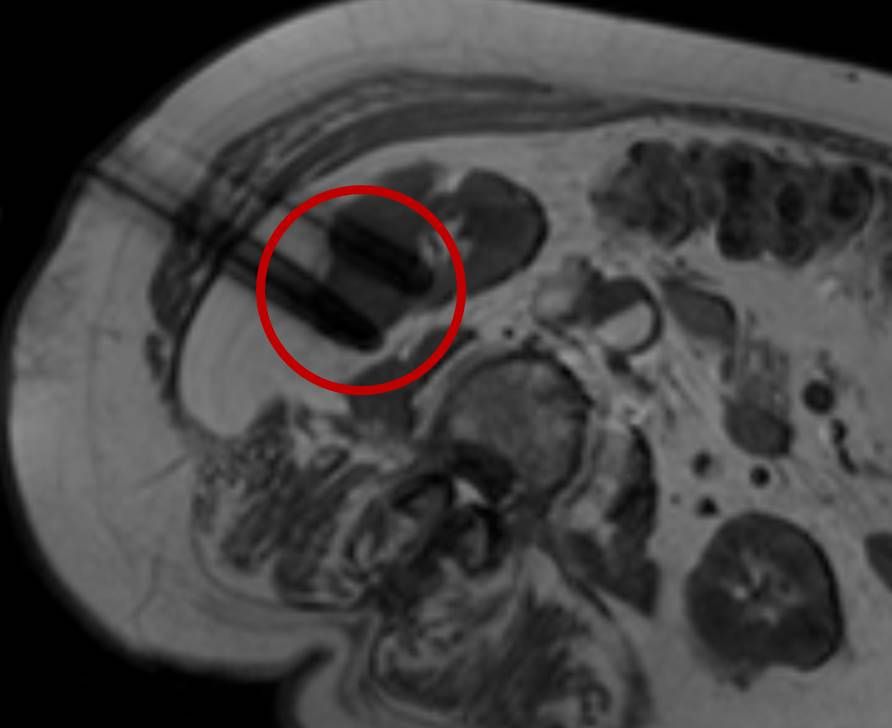

Eine Voraussetzung für die vollständige chirurgische Entfernung von Knochen- und Weichteiltumoren ist die präzise Erkennung der Tumorausdehnung und der Tumorgrenzen. Mit der Kernspintomographie (MRT) kann das Tumorgewebe exzellent von gesundem Gewebe abgegrenzt werden und somit die Ausdehnung vor der Operation bestimmt werden. Nach der kernspintomographischen Bestimmung der Tumorausdehnung werden unter kontinuierlicher MRT-Bildgebung die Grenzen des Tumors markiert. Die Marker werden mit einer Nadel ins angrenzende gesunde Gewebe eingebracht. Die Markierung kann am Tage vor der Operation durchgeführt werden. Alternativ ist die Tumormarkierung auch mit anderen bildgebenden Verfahren möglich, z.B. mit der Computertomographie oder dem Ultraschall.

Abbildung: Bei diesem Patienten wurde ein im Röntgen nur schlecht sichtbarer Knochentumor vor der Operation unter MRT-Kontrolle mit kleinen röntgendichten Spiralen („Coils“) markiert. Damit hat der Operateur eine optimale Darstellung des Tumorbereichs bzw. der Tumorgrenzen und kann gezielter, schonender und effektiver operieren.